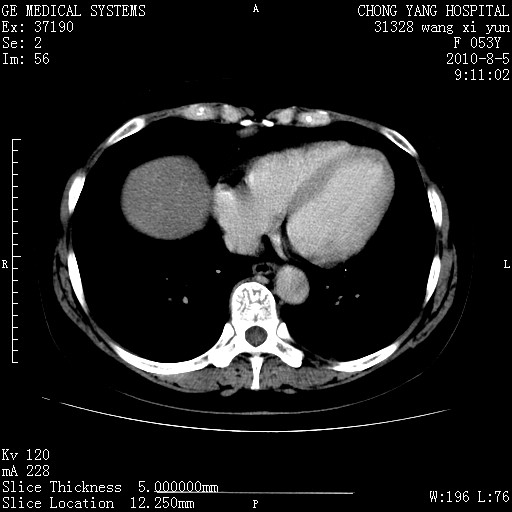

标题: CT28214:F41Y 血尿二十天,建议盆腔平扫加增强。

胆管细胞ca?

1)考虑肝左叶胆管细胞癌。2)脂肪肝。

支持胆管细胞ca。